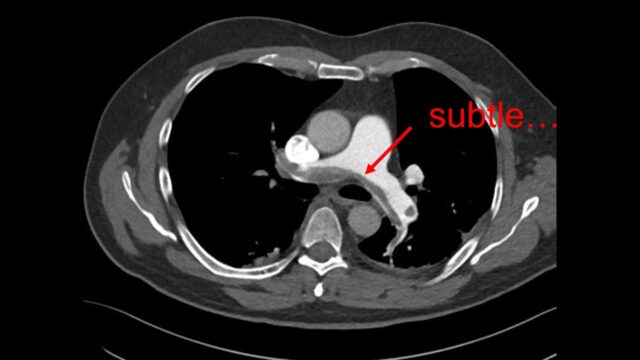

What about the CT scan itself – can this help you tease out the badness?

The classic report is the saddle PE, the huge thrombus straddling the bifurcation of the PAs. Surely this means badness? Clot burden does not make it into the PESI score or into the ESC guidelines. There are a number of papers to support that clot burden does not really predict physiology or outcomes

However I do think that an absence of clot burden suggests that PE is unlikely to be killing your patient. If I see a report of segmental or sub segmental PE in a sick patient then I’m often looking for other pathology to explain why the patient is sick.

There are two things that I do look for on the CT scan to predict severity the size of the RV compared to the left with the position of IVS

and i look for contrast reflux into the IVC. An RV under acute pressure will fail. When the RV fails it blows out and it fails to pump effectively with > contrast backing up in the IVC. If your radiologists are not reporting this routinely they should be.